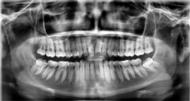

En la radiografía lateral de cráneo ( Figura 6 ) se ve la línea estética de Rickets, que el labio superior se encuentra a +0.5 mm y el inferior a -2 mm. En las mediciones cefalométricas más importantes en la figura 11 un ANB de 5º, GoGn-SN de 33º y FMA de 21º crecimiento normodivergente y Witts de -1 mm. A los criterios dentales encontramos

1-PLT de 129º e IMPA 99º proinclinación de incisivos tanto superiores como inferiores. En la radiografía panorámica (Figura 7), la presencia de 32 órganos dentarios, con terceros molares inferiores aún sin erupcionar y terceros molares superiores

7. Radiografía panorámica.